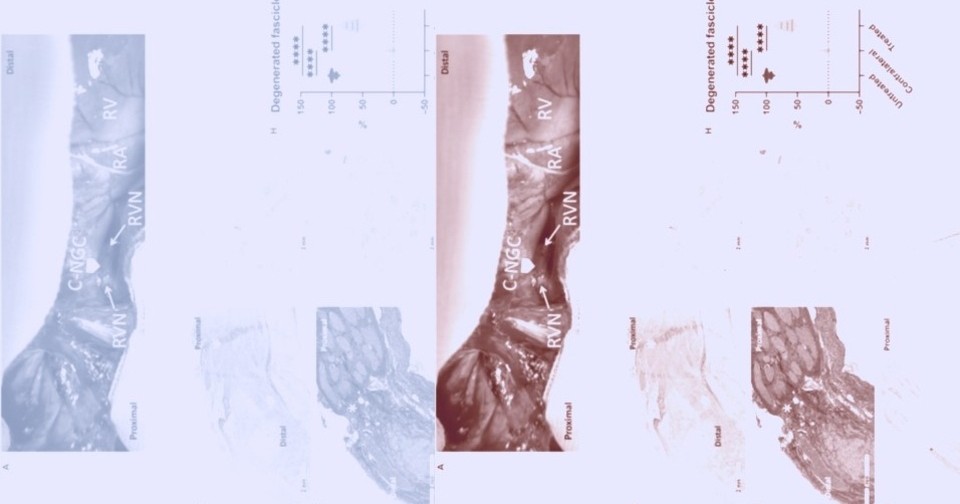

У животных из контрольной группы уже через десять дней после перерезки правого блуждающего нерва развилось смещение, или отскок, межжелудочковой перегородки в сторону правого желудочка. Такое аномальное движение перегородки нарушает синхронизированное расслабление желудочков и может свидетельствовать о нарушении наполнения левого желудочка. У минипигов после восстановления иннервации не наблюдалось отскока перегородки ни в один из моментов времени. Гистологический анализ показал, что спустя четыре месяца на пересеченных культях блуждающего нерва, помещенных в разработанную манжету, сформировался нервный мостик. Окрашивание нейрофиламентов подтвердило жизнеспособность пучков как в проксимальных, так и в дистальных культях. Восстановленные нервы сохранили физиологическое расположение пучков, аналогичное интактному контролю. Кроме того, в сердце животных из экспериментальной группы сохранялась нормальная симпатическая и парасимпатическая иннервации.

Маркеры окислительного стресса, клеточного старения и воспаления были повышены в дисфункциональных областях сердца у животных из контрольной группы. Количественный протеомный анализ, а также другие молекулярные исследования показали, что у минипигов с восстановленной иннервацией наблюдается значительно меньше признаков раннего ремоделирования сердца по сравнению с минипигами из контрольной группы.